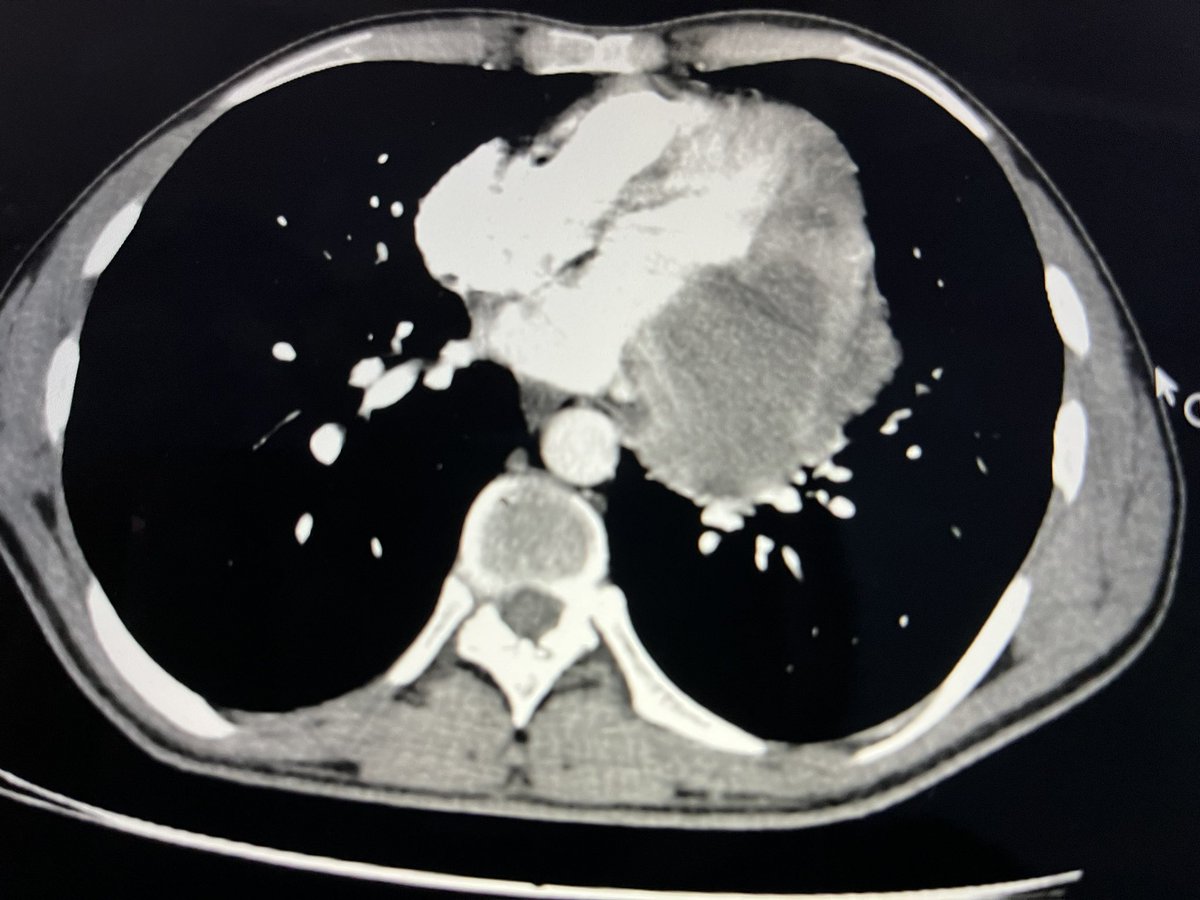

Our editorial @ASE journal. LA strain reservoir strain(LARS) is a sensitive marker of LA dysfunction. LVGLS and LARS are associated with hemodynamic severity of MAC, and are independent predictors of CV outcomes in MAC.bit.ly/47IB9u0 @iamritu @DocStrom @OchsnerCardio @pattypellikka